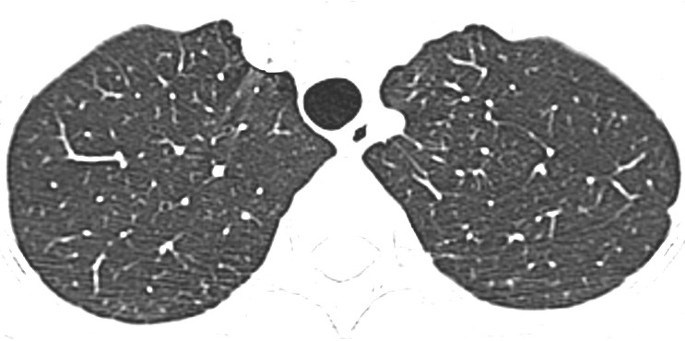

A 36-year-old lady with diffuse large B-cell lymphoma presented with neutropenic fever and cough on the 17th day of the 6th cycle of CHOP chemotherapy (cyclophosphamide, hydroxydaunorubincin, oncovin and prednisolone). Physical examination was unremarkable apart from the low grade fever (38.1°C). On admission she had a low absolute neutrophil count (ANC) (0.6x10*9/L), high erythrocyte sedimentation rate (ESR) (50 mm/h) and high C-reactive protein (CRP) level (12.3 mg/l). Chest radiograph was normal (Figure1). Initial septic workup was negative, which included sputum bacterial culture, sputum acid fast bacilli (AFB) smear and culture, bacterial and fungal blood culture, early morning urine AFB smear and culture. Thoracic CT was performed subsequently, which showed bilateral patchy ground glass opacities without zonal predominance (Figure2). Repeated sputum culture yielded heavy growth of S. maltophilia, which was sensitive to Ceftazidime, Cotrimoxazole, Levofloxacin, Ticarcillin/ Clavulanate, and resistant to Imipenem. After cessation of chemotherapy and commencement of Piperacillin/ Tazobactam (Tazocin) and Gentamycin, which later switched to Ciprofloxacin, her fever subsided and ANC normalized. Her chest radiographs were all along normal despite abnormal thoracic CT. Three months later her thoracic CT showed complete resolution of the ground glass opacities (Figure3).

To the best of our knowledge, there is only one case report describing the CT features of S. maltophilia[23]. In that case, multifocal areas of air-space consolidation, ground-glass attenuation areas, small centrilobular nodules and bronchial wall thickening were present. In our series, the sole CT finding of patient 1 is bilateral patchy ground glass opacities without zonal predominance. Air-space consolidation, ground glass opacities, numerous centrilobular nodules and bronchial wall thickening are noted in patient 2. These are similar to those described in prior case report. Compared with that reported case, the only new imaging finding in patient 2 is bilateral cylindrical bronchiectasis. Among all three cases, diffuse ground glass opacities without zonal predominance is the most consistent CT features of S. maltophilia pneumonia. Other imaging findings such as bilateral multifocal areas of air-space consolidation and centrilobular nodules can be occasionally found. Bronchiectasis likely represents the later stage of pneumonia. However, since these imaging features and pattern are not specific nor diagnostic, the final diagnosis of S. maltophilia pneumonia still relies on microbiology results.

Stenotrophomonas maltophilia is a rare yet important globally emerging opportunistic pathogen. The most consistent CT features of S. maltophilia pneumonia is diffuse ground glass opacities without zonal predominance. Bilateral multifocal areas of air-space consolidation, centrilobular nodules, bronchiectasis and bronchial wall thickening are occasionally found. Due to its supreme sensitivity, the role of thoracic CT in the detection and exclusion of pulmonary infection, including S. maltophilia pneumonia, in neutropenic febrile patients cannot be overstressed.